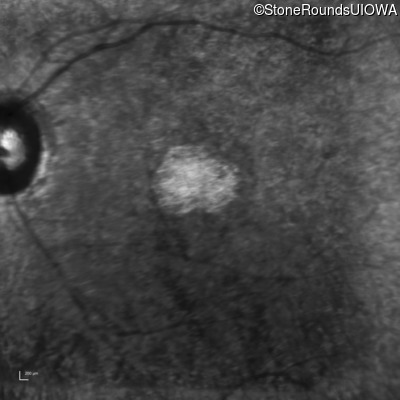

The clinical features supporting the diagnosis of Bardet Biedl syndrome in this patient include: bone-spicule-like pigmentation, narrowed arterioles and macular atrophy on ophthalmoscopy; photoreceptor loss on OCT; ulnar polydactyly, obesity, abnormal cognition, hypertension; and, normally sighted parents.